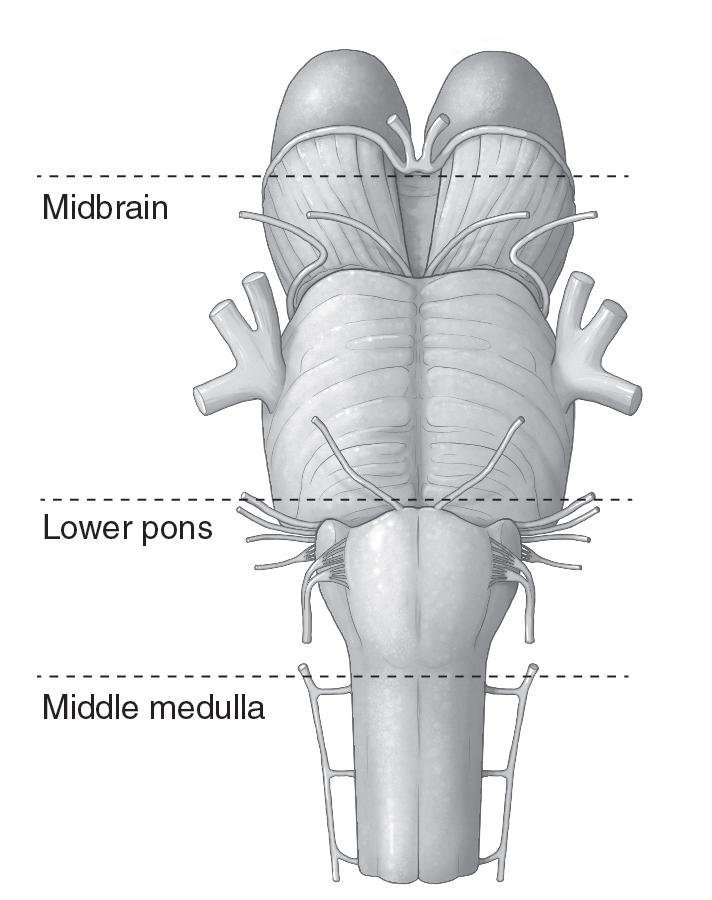

Medical Illustration

All images are works made for hire and are the exclusive property of the client. These are shown as sample purposes of my work only. For licensable work, please see my Illustration Services page.

Medical Illustrator for Precision Graphics, Lachina, and Human Kinetics Publishing (current)

Contract freelancer for many others, some examples of my work below.